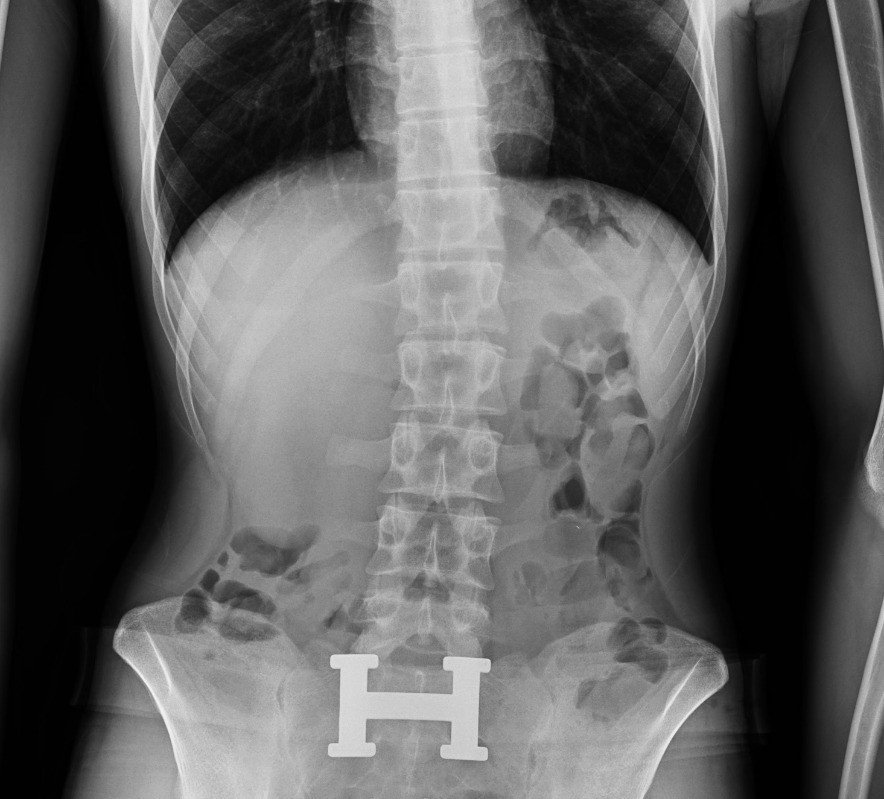

Diyarbakır’da 4 kişinin sindirim sisteminden 840 gram eroin ele geçirildi: 4 kişi tutuklandı

Diyarbakır'da şüpheli 4 kişinin sindirim sisteminden 121 parça halinde 840 gram eroin ele geçirildi.

Diyarbakır'da şüpheli 4 kişinin sindirim sisteminden 121 parça halinde 840 gram eroin ele geçirildi. Gözaltına alınan şüpheliler tutuklandı.

Araçta bulunan 4 şahsın ilk etapta yapılan kaba üst aramalarında herhangi bir suç unsuruna rastlanılmadı. Şahısların tedirgin haller sergilemesi ve rahatsızlık belirtisi vermeleri üzerine, adli makamlardan alınan karara istinaden yapılan tıbbi kontrollerde şüphelilerin vücut boşluğu/sindirim sisteminde 121 parça halinde 840 gram eroin ele geçirildi.